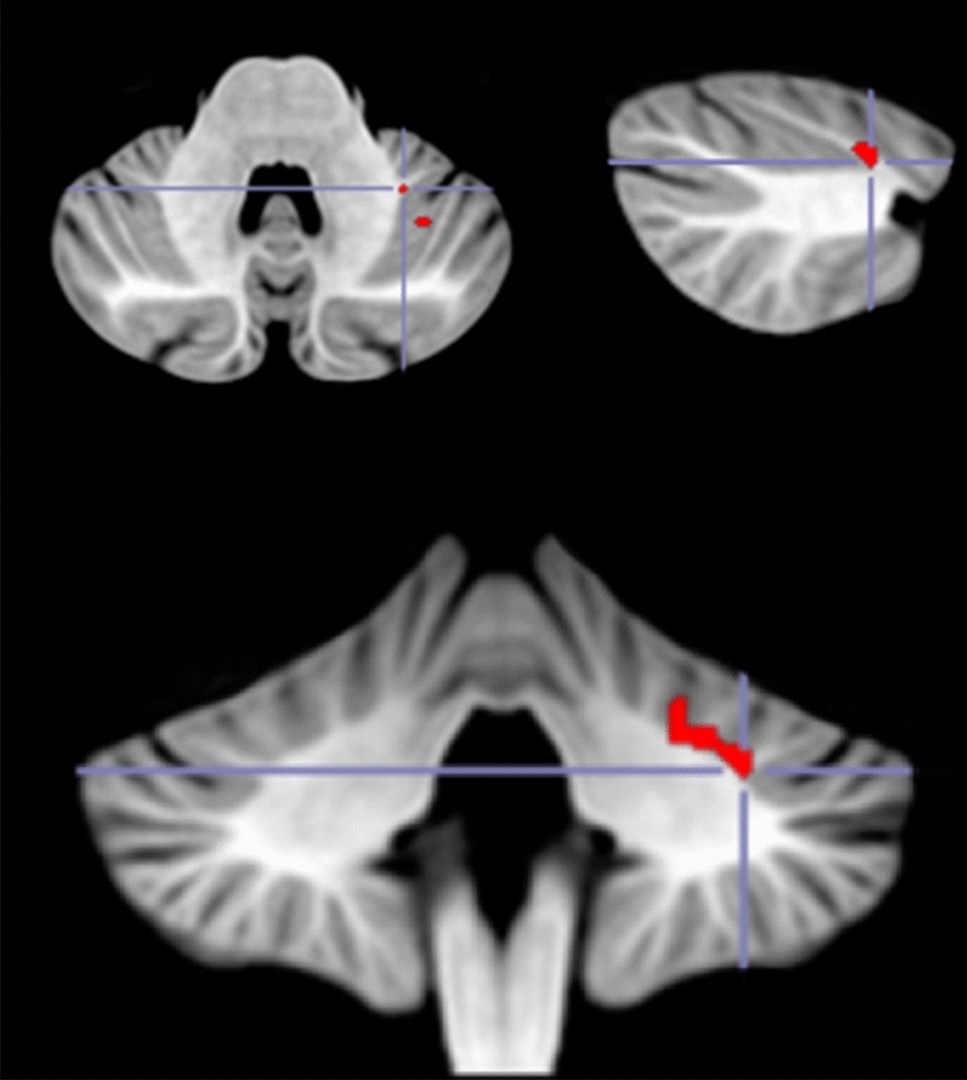

Figure 3

From: Evidence of the role of the cerebellum in cognitive theory of mind using voxel-based lesion mapping

VLSM analysis results. In red are areas of damage in the left lobule VI that were associated with a deficit in cognitive ToM. Peak MNI coordinates for the main cluster (− 30 − 46 − 34).